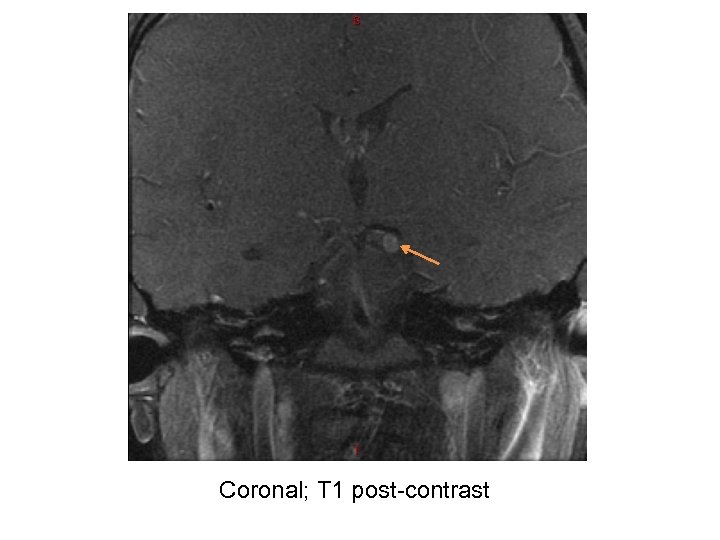

Our Patient – Diagnostic tests • MRI Brain – No obvious radiological abnormality • MRA Head and Neck – Normal • MRI Orbit (w/wo contrast): – At the left interpeduncular fossa between the left P 1 segment and superior cerebellar artery there is an enhancing 4 mm focal, round lesion involving the proximal left oculomotor nerve favored to represent a schwannoma. No connection to the vasculature seen.

Coronal; T 1 post-contrast